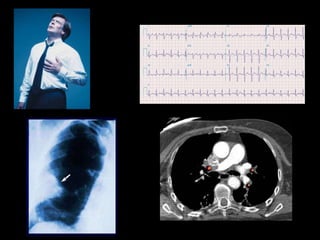

ELECTROCARDIOGRAMA

 Embolismo pulmonar.

TROMBOEMBOLIA

PULMONAR